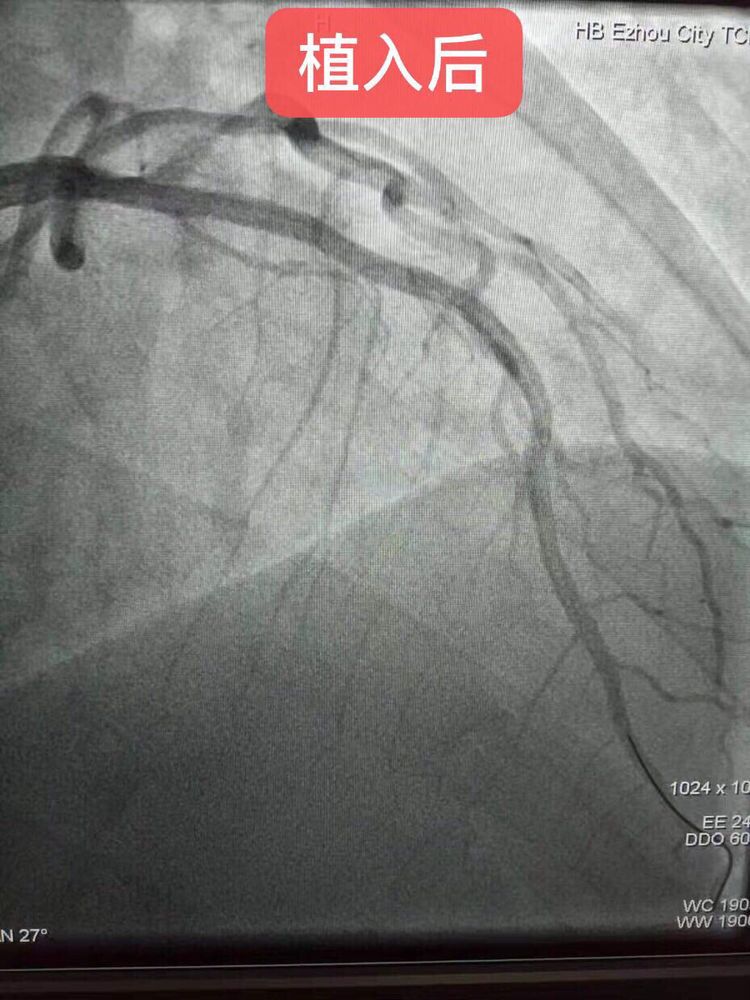

2019年9月19日,年仅36岁患者,因急性心肌梗死收治我院心内科。造影显示患者左冠前降支堵塞80%左右,鄂州中医医院洪苍浩主任,在武汉大学中南医院胡笑容教授的指导下,为这名年轻患者植入两枚生物可吸收支架(支架串联),手术非常成功!这是鄂东南地区首例,也是湖北省中医系统医院首例。(患者术后与两位术者合影,表示感谢)

此例生物可吸收支架的成功植入,标志着我院心脏介入水平和技术理念紧跟着国际国内先进步伐、迈上了一个新台阶,造福广大冠心病患者。